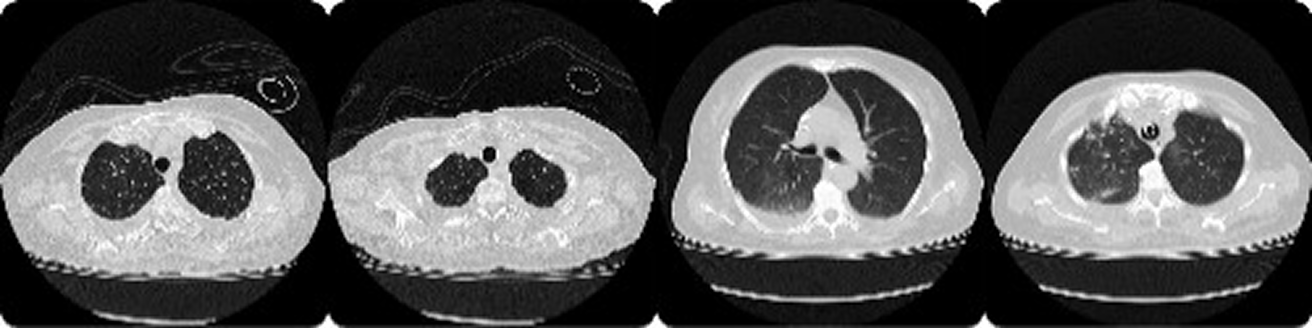

COVID-19 dataset

COVID-19

The volumes present an average of 45 slices and the spatial dimensions are 512x512 pixels. Additionally, these studies were complemented with clinical information, comorbidities, findings and their distribution and a measure that indicates the degree of severity of the disease. The evaluation was carried out by two radiologists. Regarding the severity assignment of COVID-19, carried out based on the percentage of affection of each lobe, it has the following distribution: 33 studies in mild stages, 52 in moderate stages, 46 in severe stages, 37 in critical stages. The local RX data set presents a total of 688 radiographs, which have been anonymized and previously processed to perform the various classification and segmentation tasks. The data set presents 300 annotations made by the radiologists related to the possible findings of each condition.